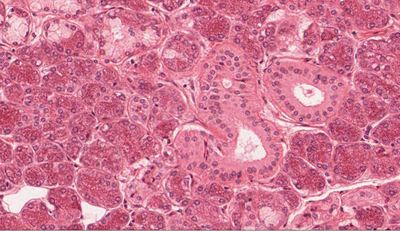

Question 10

Question

escoje la opcion correcta

Image:

075f4453-4ed5-44a7-b2ea-492744467848.JPG (image/JPG)

Answer

parotida

submaxilar

tejido conjuntivo denso

tejido onjuntivo laxo

musculo cardiaco